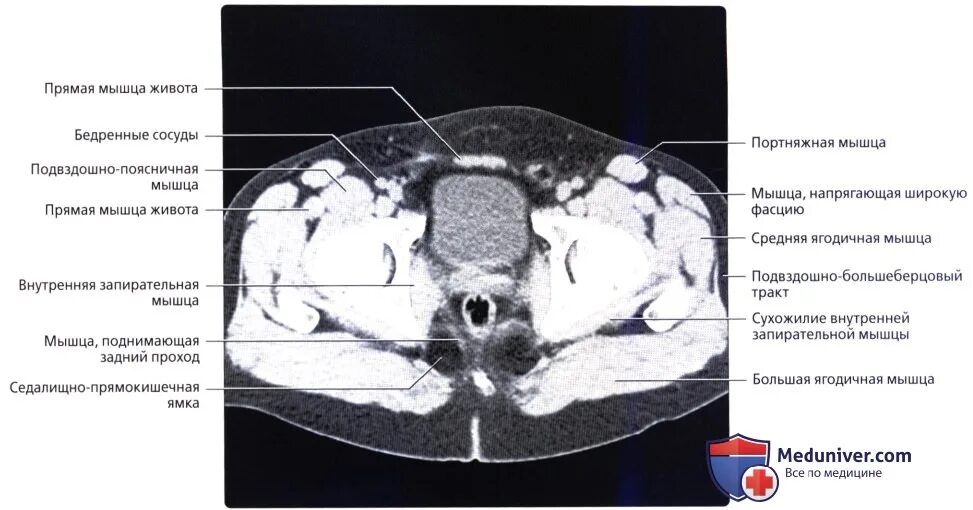

Мышца поднимающая задний проход